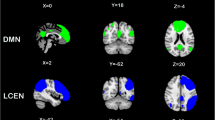

A spatial match-to-template revealed correlation (Pearson’s r) values for each of the 20 estimated independent components with resting-state networks within the CONN toolbox (i.e., salience, fronto-parietal, language, cerebellar, visual, default mode, dorsal attention, sensorimotor). Based on the highest correlation between each group spatial map and templates of resting-state networks, eight components—one for each resting-state network—were identified and extracted using a group-ICA (salience network: r = 0.37; fronto-parietal network: r = 0.26; language network: r = 0.34; cerebellar network: r = 0.31; visual network: r = 0.51; default mode network: r = 0.36; dorsal attention network: r = 0.54; sensorimotor network: r = 0.46; see Fig. 1). They were then compared between the two groups (smokers vs non-smokers) using an independent sample t-test. Smokers showed reduced connectivity within the dorsal attention network (DAN) in the left superior and middle frontal gyrus (MNI coordinates: x = −26, y = + 12, z = + 62, size = 522; T(94) = -5.26, p-FWEcluster-level < 0.001) and left superior division of the lateral occipital cortex (MNI coordinates: x = −36, y = -66, z = + 42, size = 257; T(94) = -4.99, p-FWEcluster-level < 0.001), as shown in Fig. 2. Within smokers, higher levels of CO were associated with increased connectivity within the sensorimotor network (SMN) in the left central opercular cortex. Smokers with higher consumption of daily cigarettes, on the other hand, showed increased connectivity within the cerebellar network (CN) in the left and right cerebellum and within the default mode network (DMN) in the left frontal pole; they also showed decreased connectivity within the visual network (VN) in the left paracingulate gyrus and within the salience network (SN) in the anterior cingulate gyrus (see Table 2). Moreover, a positive significant correlation between CO levels and daily cigarette consumption was found (ρ = 0.417, p = 0.004).

The left superior and middle frontal gyrus (x = -26, y = + 12, z = + 62, size = 522) and left superior division of the lateral occipital cortex (x = −36, y = −66, z = + 42, size = 257) show decreased functional connectivity within the dorsal attention network in smokers compared to healthy non-smokers.